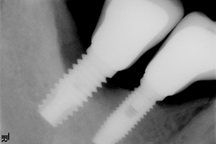

Avanzada: Profundidad de sondaje >8 mm, con sangrado y/o supuración en >2 sitios del implante, y pérdida ósea > 50% del largo del implante (Fig. 4).